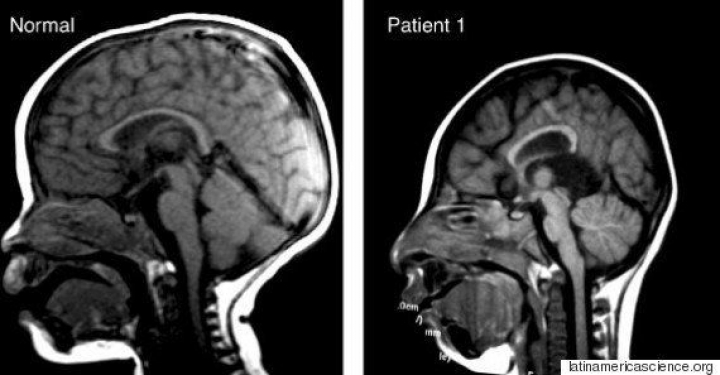

En 2014, las autoridades sanitarias de Brasil informaron de 147 casos de bebés que nacieron con el cráneo deformado: se trata de microcefalia, una deformación congénita del cráneo que comprime el cerebro. En 2015, se llegaron a dar 4.000 casos de microcefalia en el país.

La correlación entre el aumento de casos de microcefalia en Brasil y en otros 19 países del continente en el año 2015 y la propagación del virus del Zika es tan evidente que muchas autoridades sanitarias ya han aceptado la hipótesis de que lo que causa estas deformaciones en el cráneo es el virus, transmitido por la picadura de un mosquito a la madre durante el embarazo. Se ha encontrado material genético del virus del Zika en el líquido amniótico de las madres que dieron a luz a bebés con microcefalia y en el cerebro de dos bebés que murieron por la enfermedad.

Esta radiografía de Colombia compara el cráneo de un bebé normal con el del "Paciente 1", un bebé cuya madre contrajo el virus del Zika durante el embarazo.(latinamericascience.org)